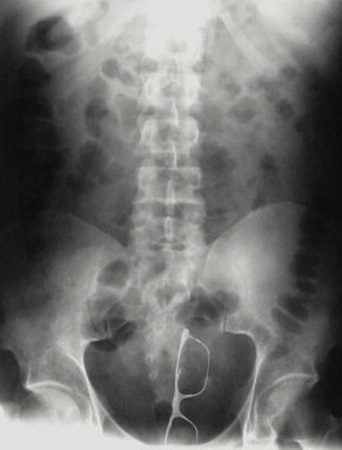

Задница — не самый лучший футляр для очков